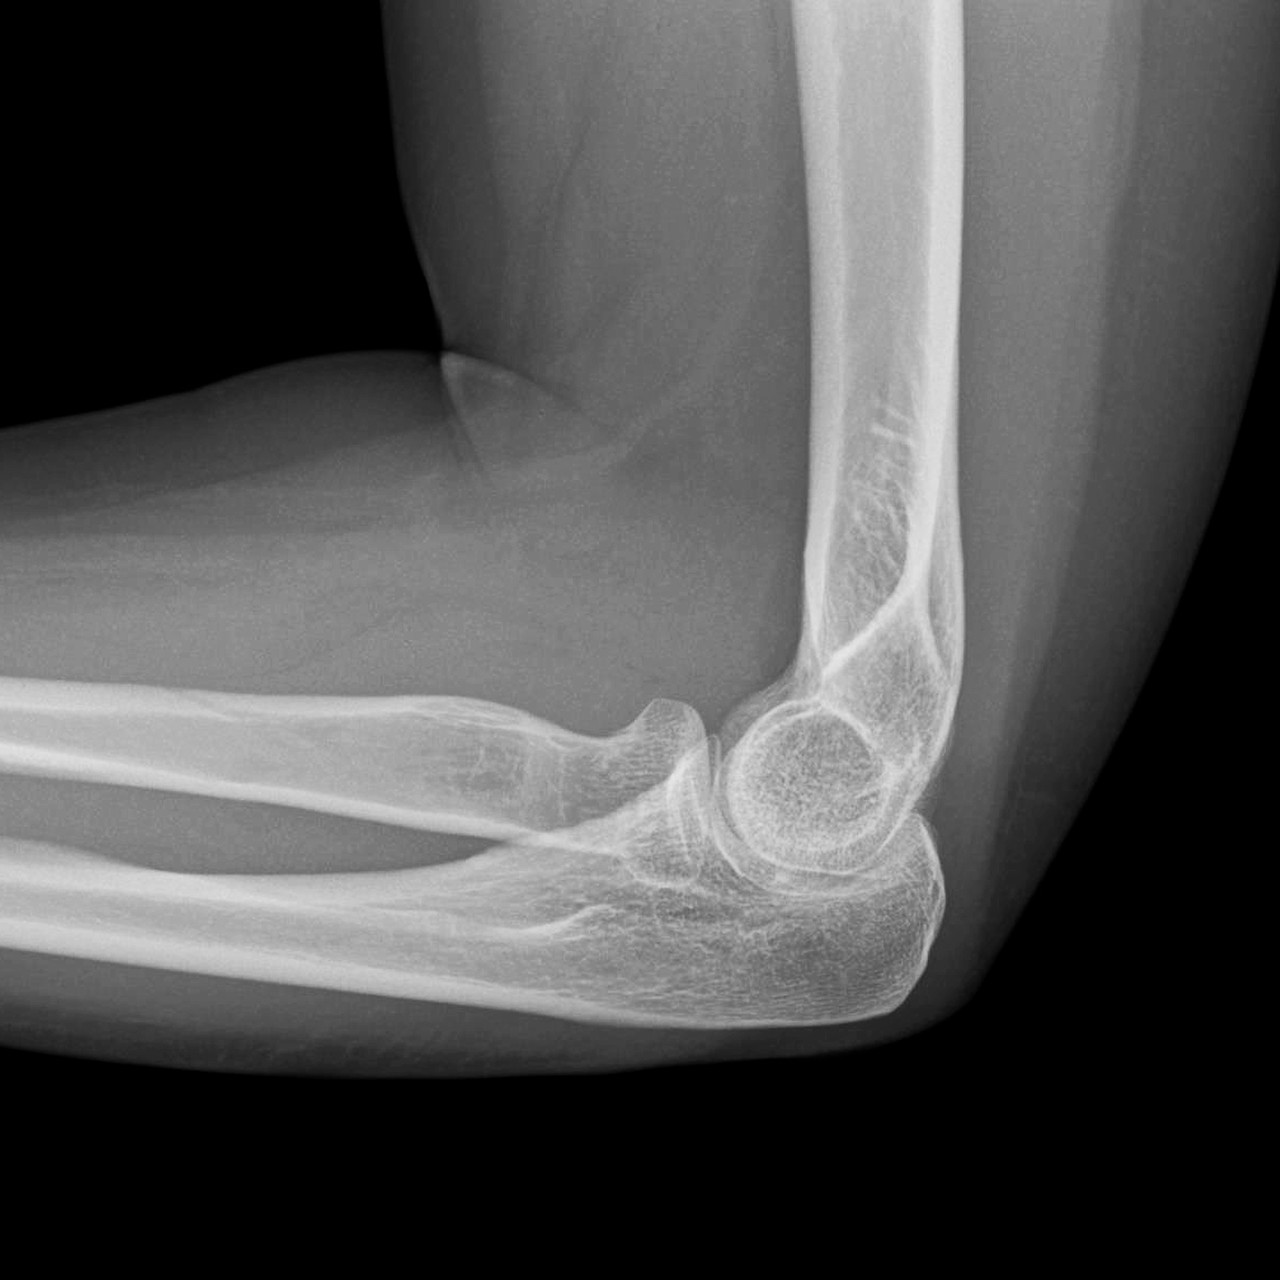

성모탑정형외과의 영상의학 검사는 먼저 방사선검사(x-ray)로 확인하여 석회나 다른 질환으로 인한 통증은 아닌지 등을 확인합니다. 팔꿈치 상과염은 대부분 간단한 초음파검사로 진단 가능합니다.